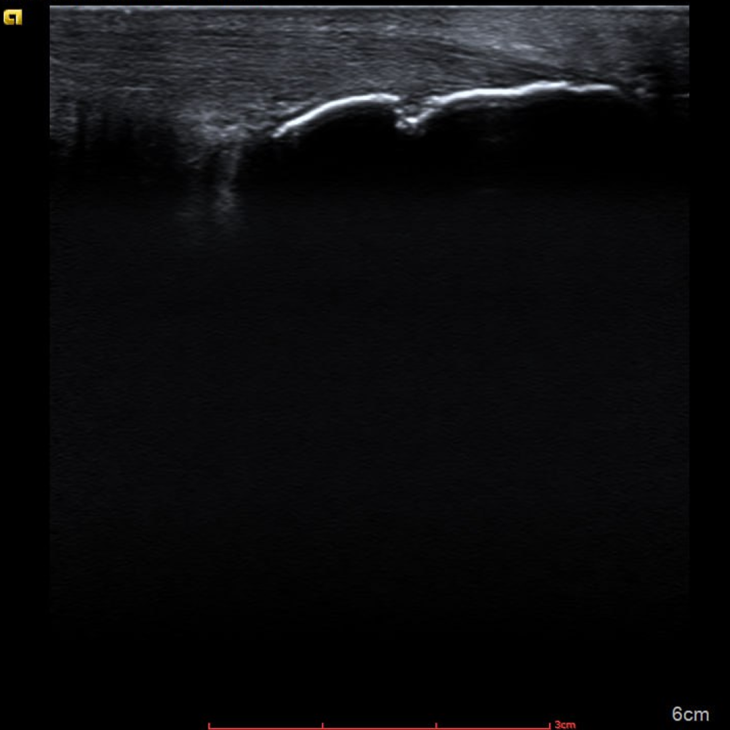

УЗД — чіткі ознаки структурного ураження:

• ерозії кістки;

• синовіт;

• випіт у суглобах.

Важливий момент: саме результати УЗД стали переломним фактором — пацієнт побачив реальні зміни й почав дотримуватися лікування.

УЗД дає можливість:

• виявити ураження раніше, ніж рентген;

• оцінити м’які тканини та ентезиси;

• контролювати активність запалення;

• підвищити довіру пацієнта до лікування.